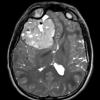

NEOPLASMS (EMBRYONAL)

CNS-BCOR ITD (2)